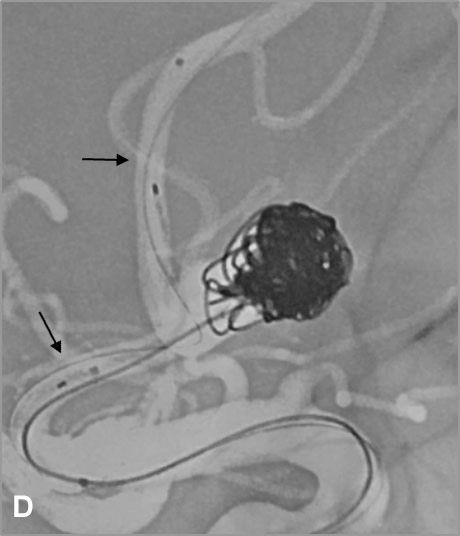

D, E, F: Tratamiento mediante “coiling”, inicialmente simple, posteriormente asistencia con stent mediante técnica “jailing” obteniendo compactación óptima de las espiras (las flechas negras indican las marcas radiopacas proximal y distal del stent; las flechas blancas muestran la permeabilidad de las arterias adyacentes al cuello aneurismático tras el tratamiento).

Ante la necesidad de implantación de stent se comenzó doble antiagregación una semana antes del tratamiento. Se inició el procedimiento mediante “coiling” simple, pero ante el riesgo de comprometer las arterias adyacentes se completó con “coiling” asistido con stent mediante la técnica “jailing”3, dejando el extremo distal del primer microcatéter en el interior del saco aneurismático interponiéndolo entre la malla del stent y la pared arterial. Tras desplegar el stent (Neuroform Atlas®) se completó el tratamiento, consiguiendo una compactación óptima de los “coils”, y evitando la protrusión de espiras que pudieran comprometer las ramas arteriales adyacentes, de especial interés en este caso.